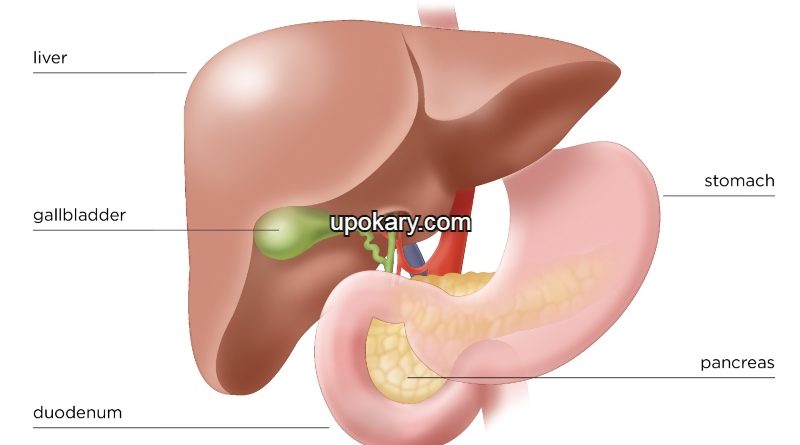

অগ্ন্যাশয় ক্যান্সার (pancreatic cancer) একটি ক্যান্সার যা অগ্ন্যাশয়ের যে কোনও জায়গায় হতে পারে। অগ্ন্যাশয় আমাদের পেটের উপরের অংশের একটি অঙ্গ। এটি খাদ্য হজম করতে সহায়তা করে এবং ইনসুলিনের মতো হরমোন তৈরি করে।

অগ্ন্যাশয় দুটি গুরুত্বপূর্ণ হরমোন উৎপাদন করে একটি গ্লুকাগন এবং অন্যটি ইনসুলিন। অগ্ন্যাশয় শরীরকে চর্বি, শর্করা এবং প্রোটিন হজম করার জন্য এনজাইম তৈরি করে হজমে অপরিহার্য ভূমিকা পালন করে।

অগ্ন্যাশয়ের ক্যান্সার হয় যখন পাক্স্থলির পিছনের একটি গ্রন্থি অগ্ন্যাশয়ের কোষ আনিয়ন্ত্রিতভাবে বৃদ্ধি পেয়ে একটি পিণ্ড সৃষ্টি করে। এই ক্যান্সার কোষগুলো শরীরের অন্য অংশে আক্রমণ করতে পারে। অগ্ন্যাশয়ে বিভিন্ন ধরনের ক্যান্সার হতে পারে।

- পিত্তথলি বা লিভার ফোলা